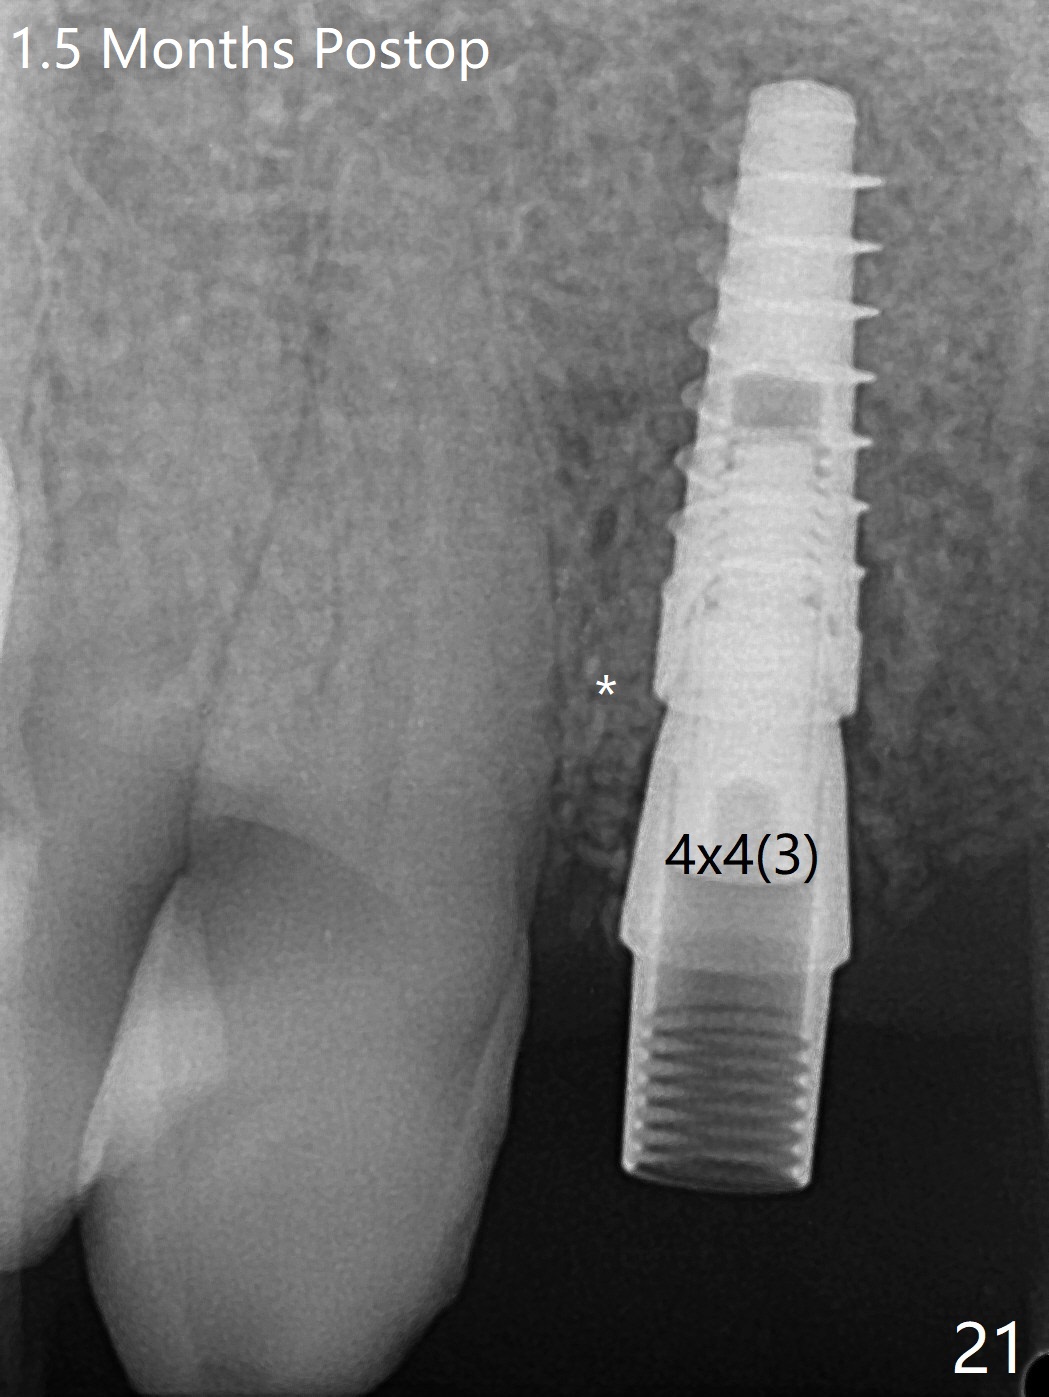

今天下午进入治疗室,粘性骨粉已制备:上清液来自红管(含促凝剂),离心3分钟(图一);再离心10分钟上清液就转变PRF,压制后,使用前剪成三块(图二:黑线),其中两块punch一个洞(图二:圆圈),插入7,9号牙基台固定;大块覆盖11/12号牙牙槽窝(图十四)。7,9,11,12号牙必须拔除(图三),然后在7,9,12种植。由于缺失左下磨牙,前牙垂直距离减少(图四)。完成9号牙位钻洞后,利用fixture mount(图五:M)植入植体,并留在原位固定导板(图六),然后7号牙种植,也留下fixture mount(图六:7,9),最后完成12号牙植入,但是后者扭力低,放置愈合螺帽(图九),而7,9号牙位放置修复基台(图七,八(使用5.5毫米profile drill后),好像基台没有完全就位。7号牙位更换基台似乎没帮助(图十),9号牙位再次放置同一个基台临床上仿佛有改变(比较图八与十二)。放置粘性骨粉后(图十一至十三),牙槽窝口覆盖PRF膜(图十四:P(A:基台)),最后使用树脂敷料固定骨粉和膜(图十五,六),基台帮助敷料固位,没有咬合干扰(图十七:*)。树脂敷料部分解决美观问题,一个月后撤除,如果植体仍有稳定性,可能制作7-10临时牙桥,可能部分维持或者恢复牙龈外形。术后一周病人主诉后面植牙和鼻底疼痛,11号牙根尖牙龈充血(图十八),轻度触痛,可能与术中尚未完全清创有关(图十九(术前CT 3D图像))。再服用Amoxicillin一周,症状好转,鼻底轻度触痛(图二十)。术后1.5月没有任何不适,撤除树脂敷料,7号牙基台(袖)显得太长,换一个短的(4.5x4(5)(图十,十一)->4x4(3)毫米)毫米),植骨好像愈合正常(图二十一:*)。7号牙换了短的基台,9号牙基台高度调整后,与对合牙有足够空间做临时牙桥,最好8,10号牙位牙龈应该凹陷(图二十二:*),有pontic外形。另外9号牙基台颊侧牙龈边缘有所修整,临时牙桥准备。先做7-10临时牙桥,理想临时牙桥pontic处树脂应该多些(图二十三:白线)压迫牙龈形成凹陷。11,12号牙牙槽窝在树脂(Bosworth)敷料下也正常愈合(图二十四)。